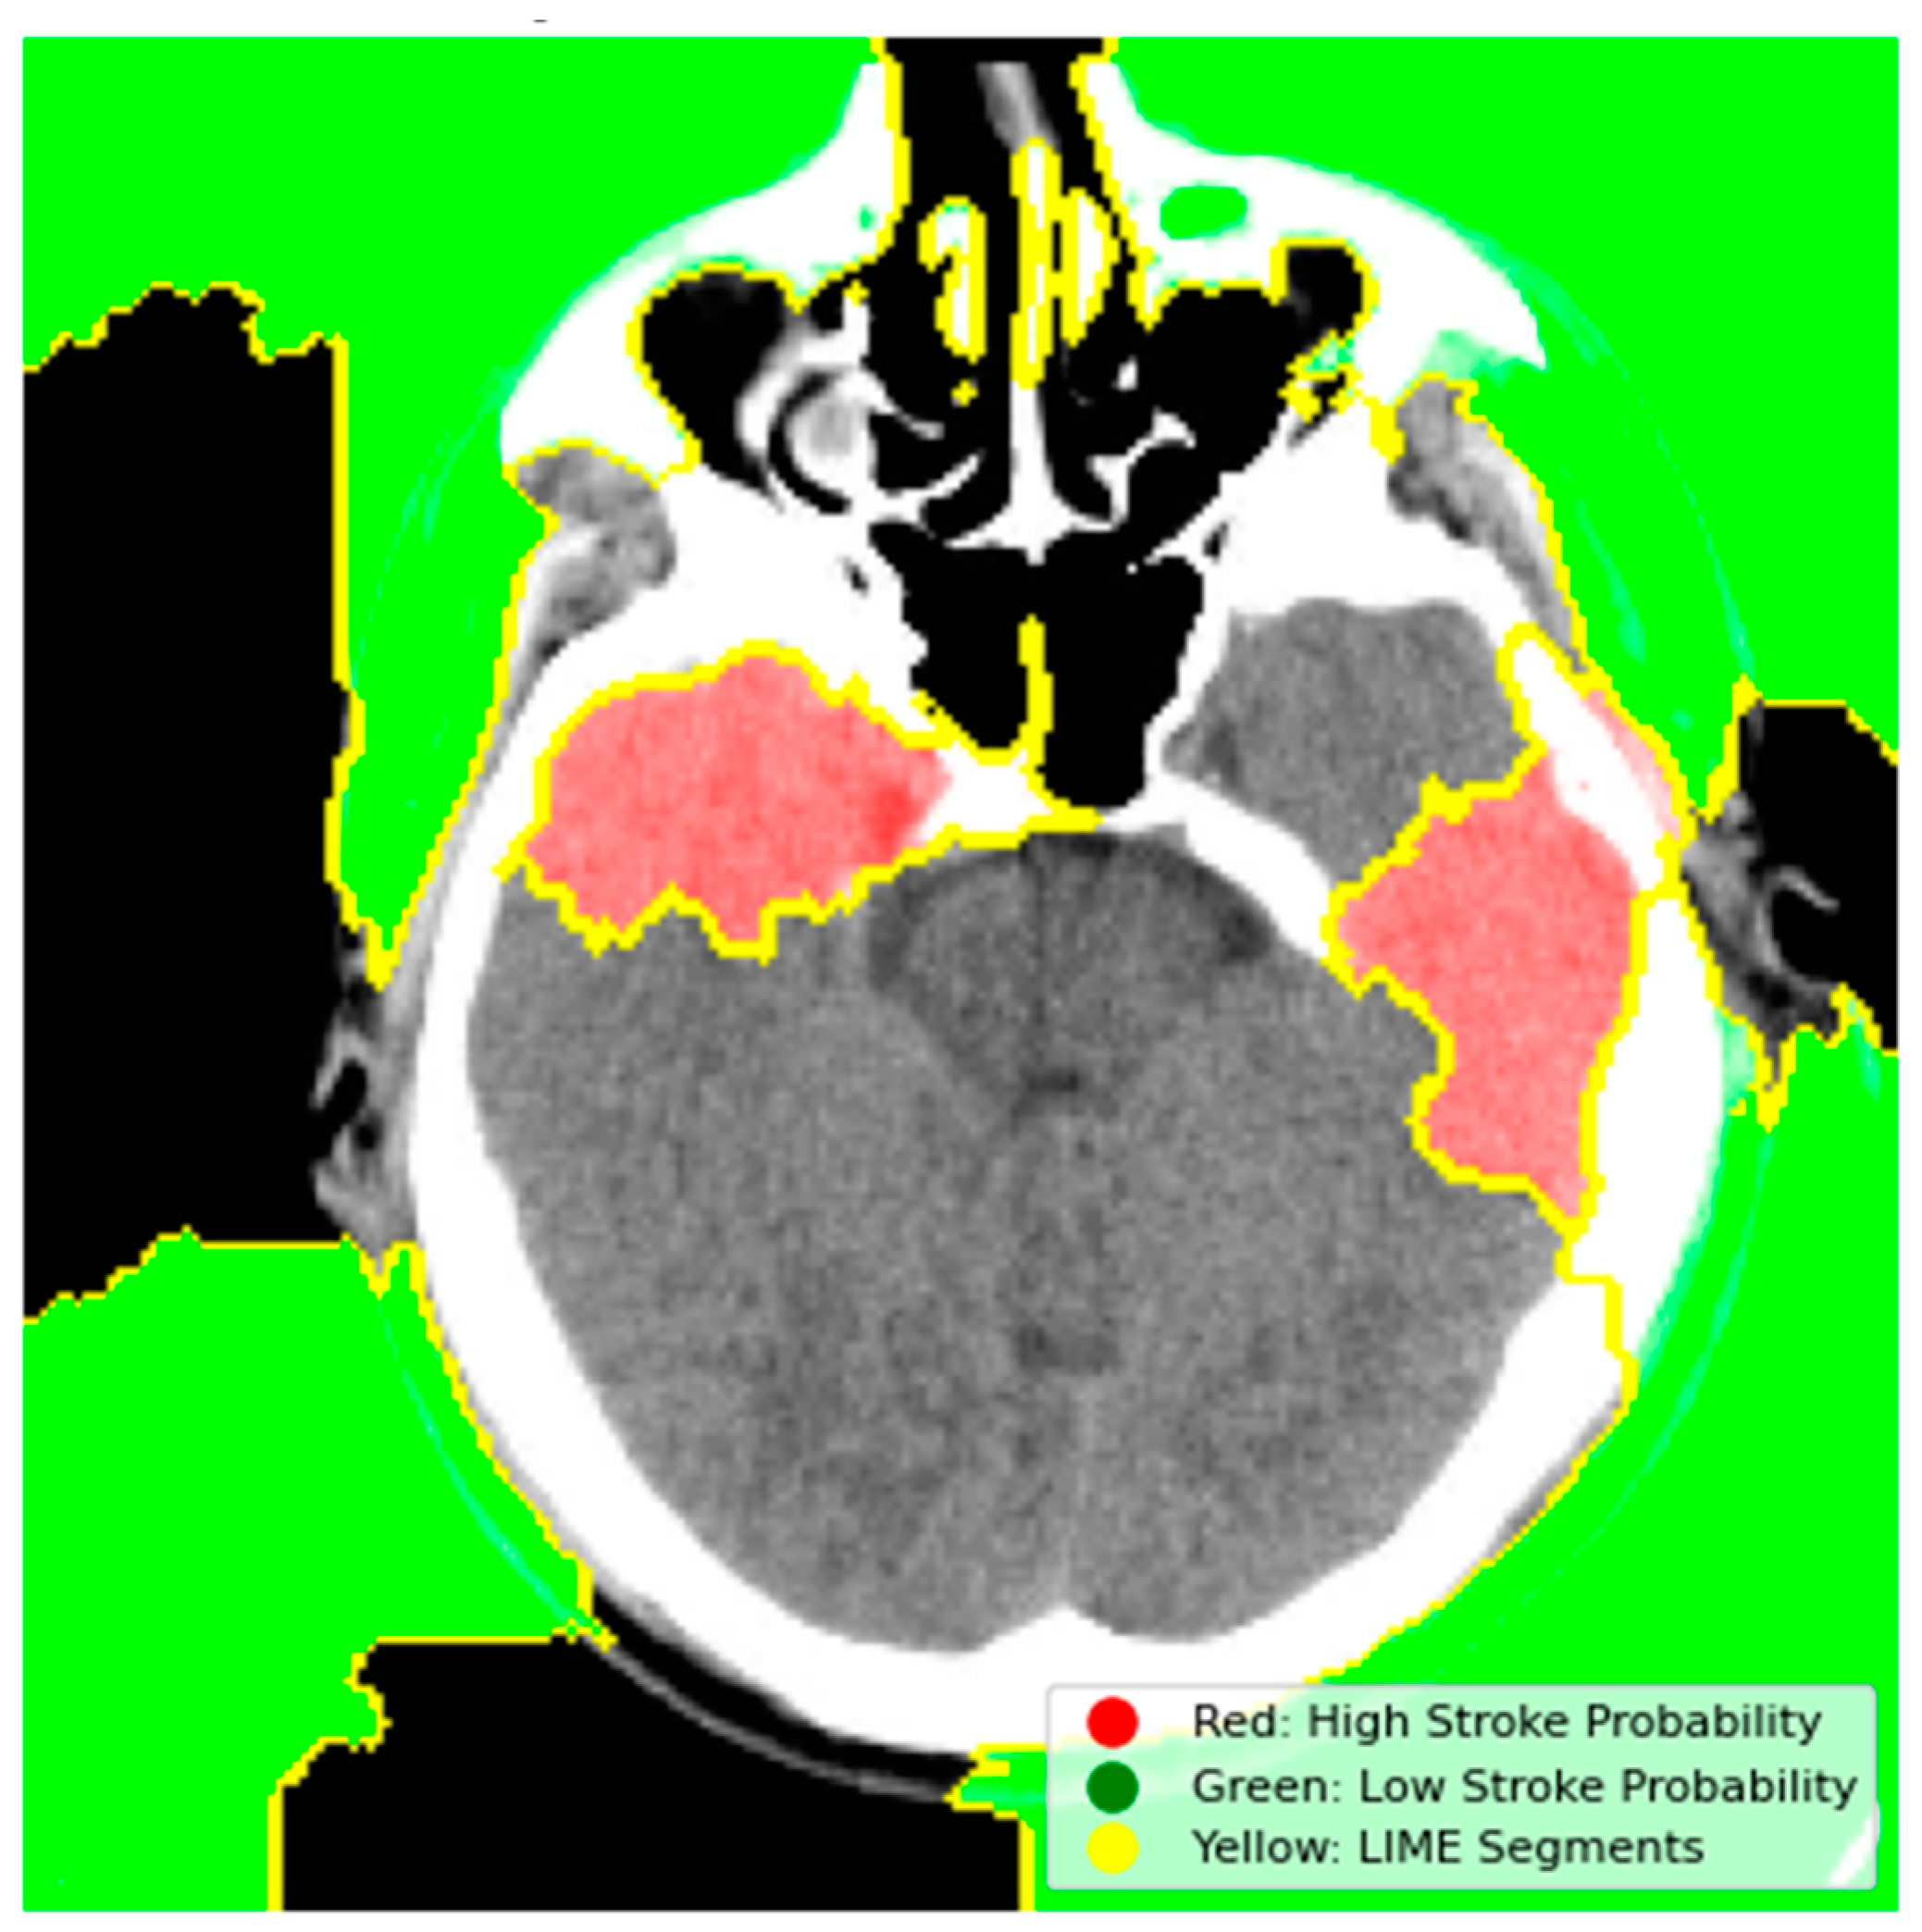

4.6.1. Model Explainability Using LIME

- Red Regions (High Stroke Probability): These areas, highlighted in red, represent regions where the model detected features strongly associated with stroke, such as hyperdense hemorrhagic lesions or ischemic hypoperfusion. The red regions in the left hemisphere, for instance, correspond to the hyperdense clot, a key indicator of a hemorrhagic stroke.

- Green Regions (Low Stroke Probability): Green areas indicate regions with minimal influence on stroke prediction, typically healthy brain tissue or non-stroke-related anatomy.

- Yellow Outlines (LIME Segments): The image is divided into superpixels marked by yellow boundaries. LIME perturbs these segments to assess their impact on the model’s prediction. By masking and observing the changes in the prediction, LIME identifies the critical regions that drive the model’s decision-making process.